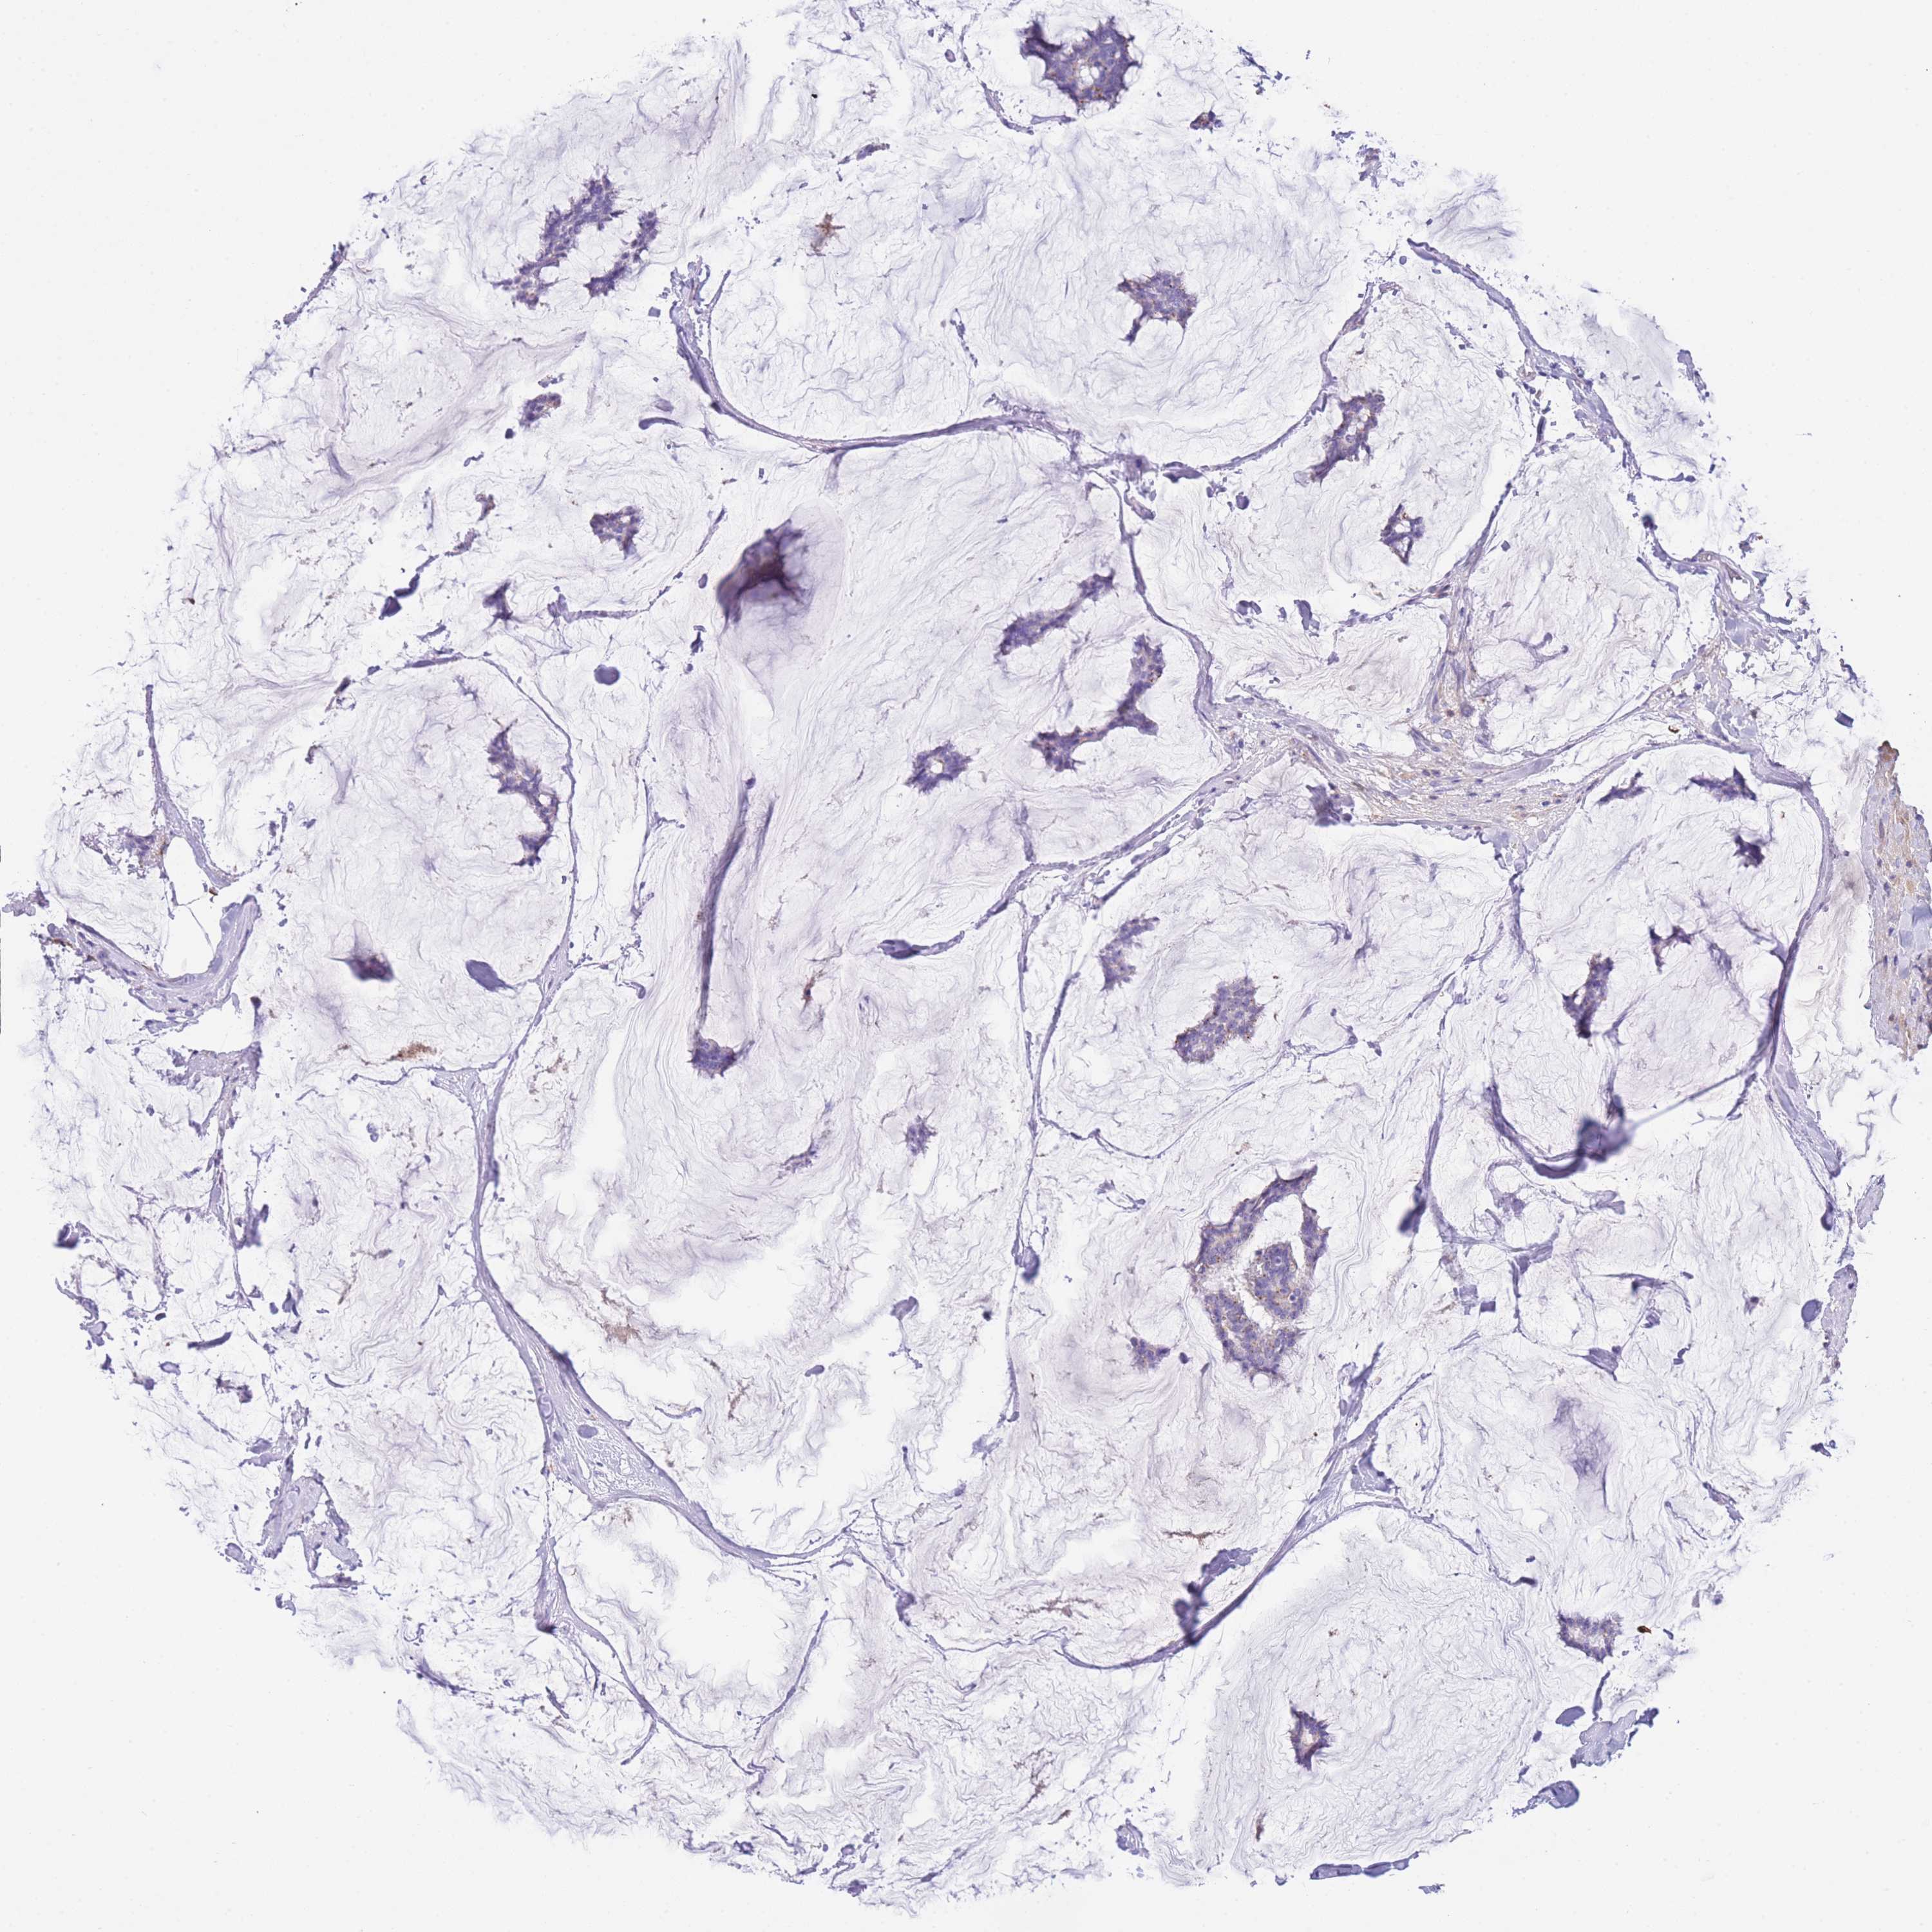

CANCER BREAST CANCER Show tissue menu

BRCA TCGA BRCA VALIDATION PROTEIN EXPRESSION